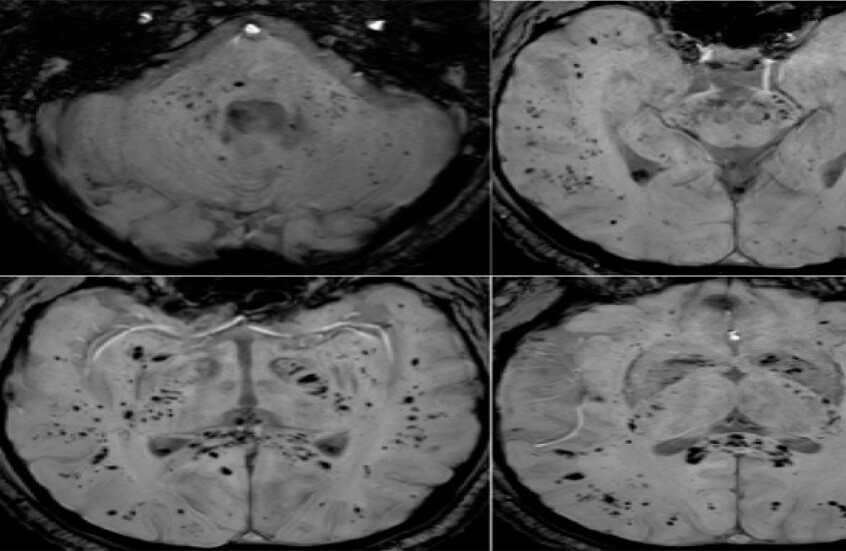

وأوضح الباحث الرئيسي الدكتور كيران تاباليا أن الفريق استخدم طرق التصوير بالرنين المغناطيسي متعددة الوسائط لدراسة المادة الرمادية والبيضاء في الدماغ، وهي مهمة للذاكرة والوظائف الإدراكية والصحة العامة للدماغ. ووجد الباحثون اختلافات ملحوظة في أنسجة الدماغ وموادها الكيميائية العصبية وشدة الإشارة وبنية الأنسجة لدى المتعافين من كوفيد-19، حتى في حالات الإصابة التي اعتبرت بسيطة.

وأضاف تاباليا: “تبين أن التغيرات في أنسجة الدماغ مرتبطة بشدة الأعراض”، ما قد يفسر مشكلات إدراكية طويلة الأمد مثل تدهور الذاكرة والتركيز، والتي قد تستمر لشهور أو حتى سنوات بعد الإصابة.